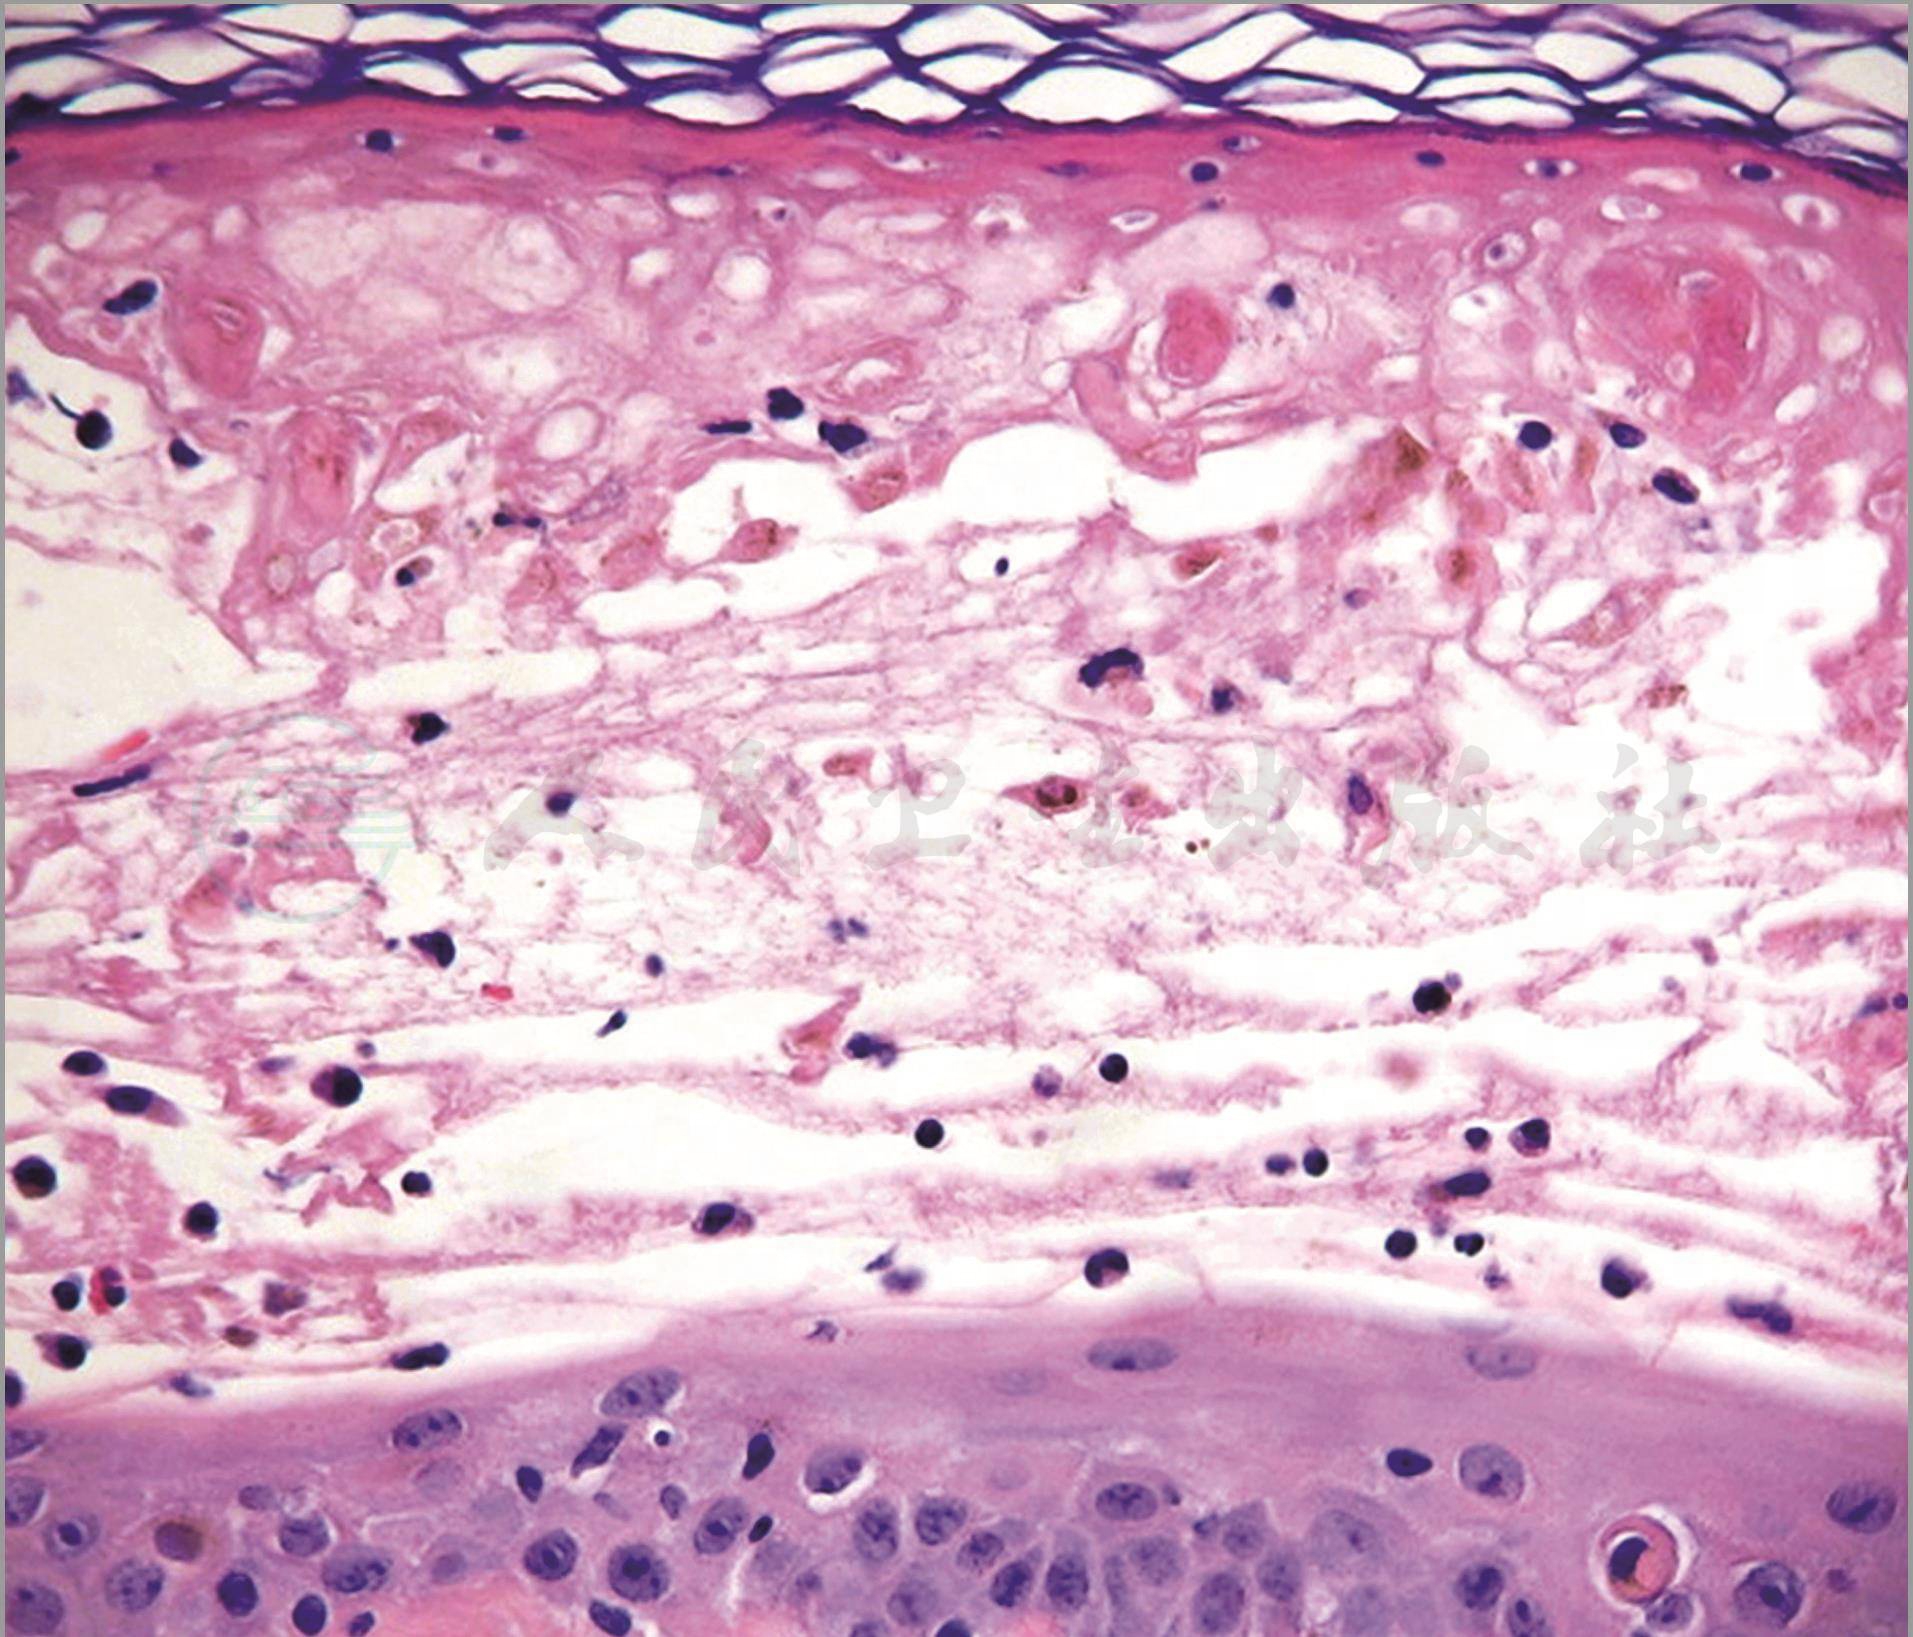

病理表现类似多形红斑。表皮细胞融合性坏死致水疱形成。真皮炎症反应轻微(图4~5)。

图4多形红斑型药疹:病理表现类似多形红斑,角质层正常,表皮细胞融合性坏死致水疱形成,真皮炎症反应轻微

图5多形红斑型药疹:示网篮状角质层及表皮内坏死的角质形成细胞